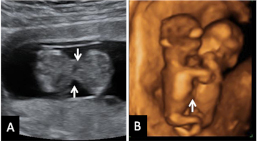

Ecografía 4D semana 11: Siameses unidos por el abdomen

La ecografía en 4D (vídeo) no deja lugar a dudas. Se trata de un embarazo de siameses de 11 semanas de gestación, que están unidos por la zona abdominal, ya que comparten una pequeña parte de hígado. La movilidad de los bebés es reducida, como vemos en las imágenes, debido a la unión de sus cuerpos. Uno de los hermanos (el de la derecha) mueve la cabeza hacia atrás, mientras las piernas se entrecruzan. Los especialistas siguen este tipo gestaciones muy de cerca y valoran la separación quirúrgica de los bebés, una vez que se produce el parto.

El embarazo de siameses (o gemelos unidos) tiene lugar cuando la división del cigoto se produce de forma tardía, entre los días 13 y 15 tras la fecundación. Como la división embrionaria es incompleta, acaban compartiendo órganos: se considera una malformación grave del embarazo de gemelos. Afortunadamente sólo sucede en el 0,06 por ciento de las gestaciones gemelares.